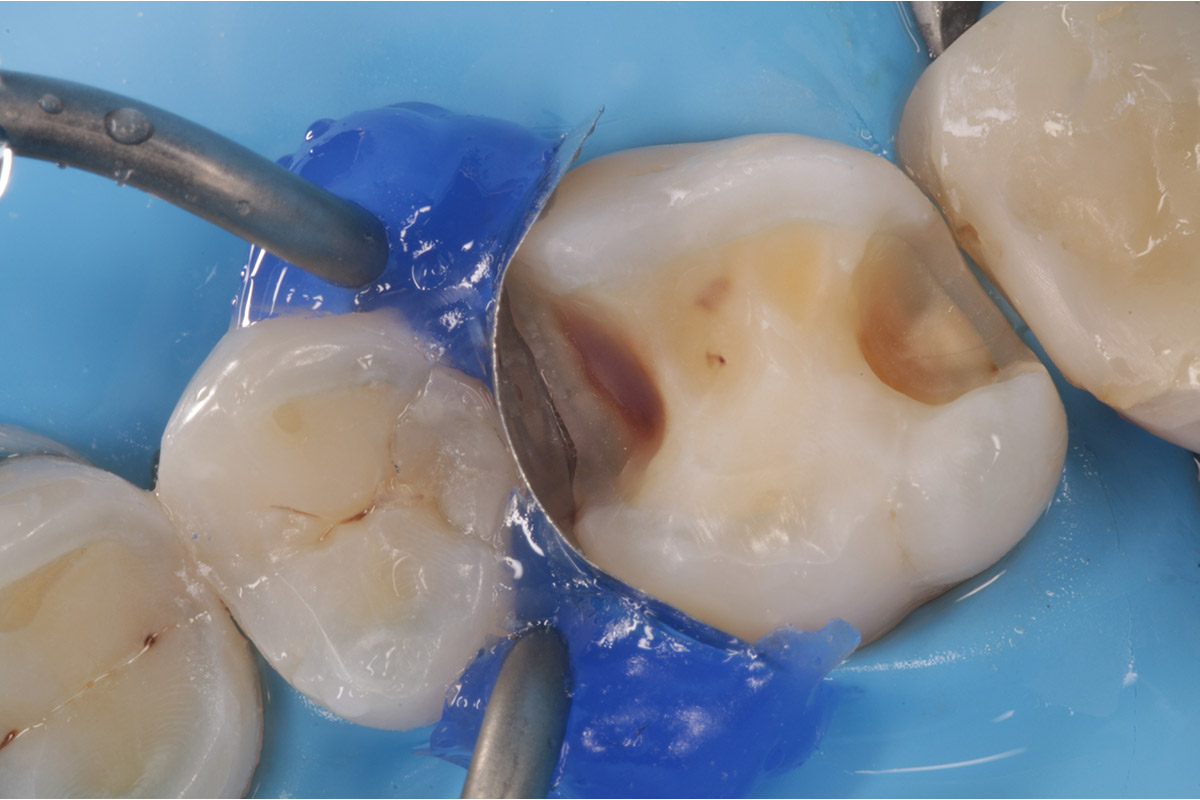

Posterior Case

Courtesy of Dr R. Asparuhov, Bulgaria